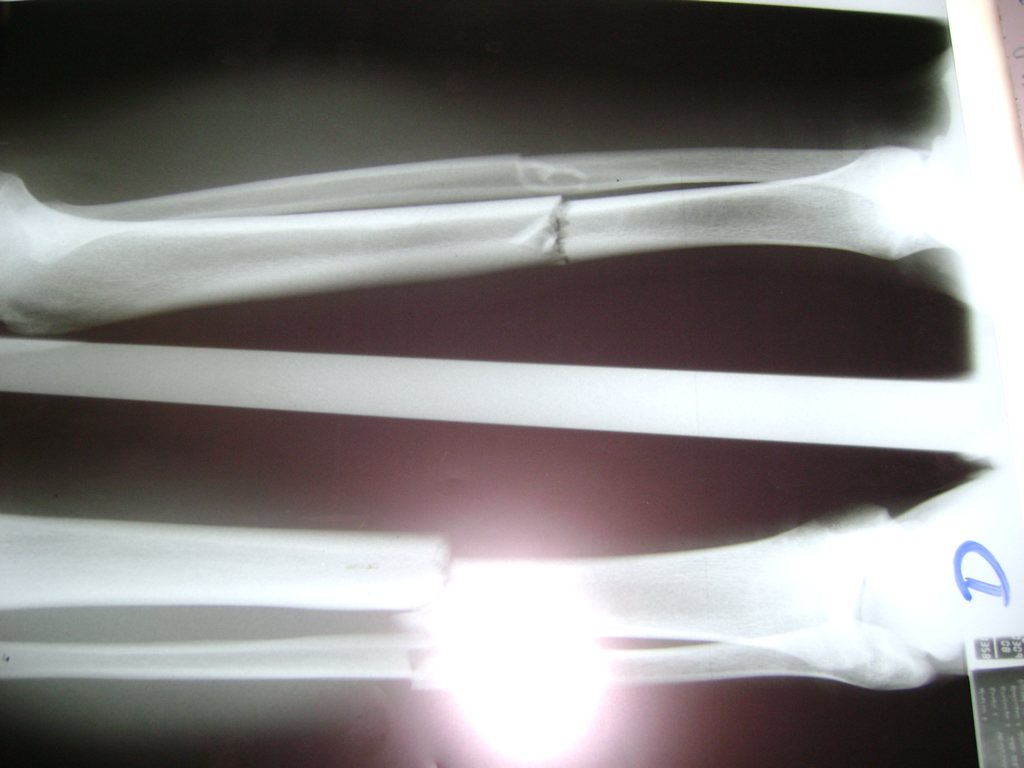

Cirugías de Peroné y Tibia

Aunque cada uno de estos huesos puede fracturarse por separado, normalmente la rotura es una lesión que se produce de forma conjunta

La mayor parte de las roturas implican a la parte proximal del hueso (parte del hueso próximo a la rodilla) o a la parte distal (parte del hueso cerca del tobillo).

Debido a la fina cobertura de piel que recubre la tibia y el peroné, las fracturas generalmente son abiertas, es decir, el hueso roto rasga la piel, atravesándola. Las fracturas de tibia y peroné generalmente se producen por un fuerte impacto o torsión.